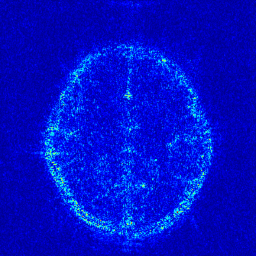

We take the difference between the absolute reconstruction error of zero-filled and the compared CS-MRI methods and only keep the nonnegative values, which can be formulated as

md=(|xfsx¯p||xfs𝒵(y)|)+.subscript𝑚𝑑subscriptsubscript𝑥𝑓𝑠subscript¯𝑥𝑝subscript𝑥𝑓𝑠𝒵𝑦m_{d}={\left({\left|{{x_{fs}}-{\overline{x}_{p}}}\right|-\left|{{x_{fs}}-{\cal Z}(y)}\right|}\right)_{+}}. (8)

Where the operator ()+subscript{\left(\cdot\right)_{+}} set the negative values to zero. We only keep the nonnegative values in the map, which results the filtered difference map. We show the corresponding filtered difference map mdsubscript𝑚𝑑m_{d} in figure 3 in the range [0 0.2]. The bright region means the better accuracy of zero-filled reconstruction. We observe the zero-filling reconstruction provide better reconstruction accuracy on some regions, indicating the information loss in the reconstruction occurs.

Figure 3: The filtered difference map d𝑑d between the reconstruction errors of the zero-filled reconstruction and recent CS-MRI inversions.